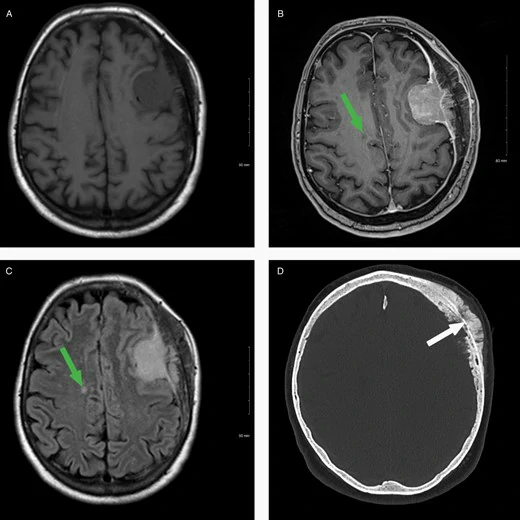

Життя після операції — більше ніж просто відновлення

Коли операція позаду, настає час відновлення. Це не просто фізична реабілітація. Психіка також потребує уваги, адже це може бути складніше, ніж очікувалося. Післяопераційні симптоми? Головні болі, запаморочення чи навіть когнітивні збої. Вони можуть стати частиною твого життя… або лише тимчасовими гостями.